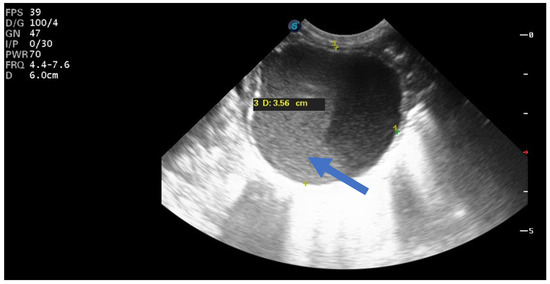

In 25% of cases, the cyst had the appearance of a complex cyst. On ultrasound, we observed the presence of internal echoes, indicating the presence of intracystic hemorrhage with round or crescent-shaped echogenic areas due to retraction of intracystic clots. We also noted fluid levels (liquid level) and sometimes the presence of microcalcifications at the level of the cyst walls (Figure 4).

Figure 4.

Ultrasound axial view. Right ovarian complex cyst in the 32nd week of pregnancy with a size of 6/4 cm and an echolucent stratification (arrow) corresponding to a hemorrhagic ovarian cyst.